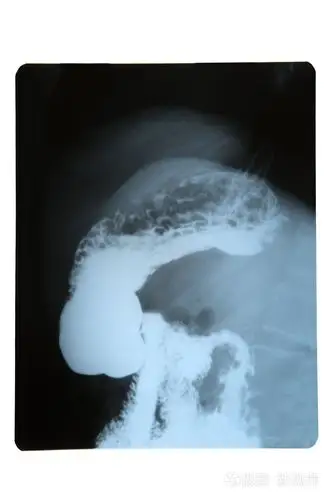

胃的x线

钡餐检查发现胃后壁米粒大小的东西 附片子,请各位同行们给看看是什么

5 分钟读懂消化道造影片(胃篇)